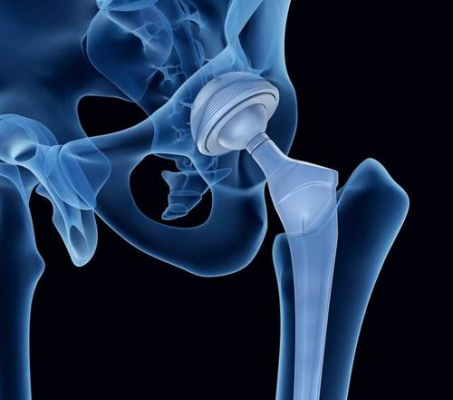

对于晚期股骨头坏死病人来说,人工全髋置换术是最有效地缓解疼痛、改善髋关节活动度和恢复正常日常生活的手术方法。

对于出现骨性关节炎的患者,只能将关节置换作为最佳选择。由于此类患者关节置换效果较其他患者差,因此在出现骨性关节炎前,采取各种保存股骨头的治疗方法延缓病程的发展,推迟全髋置换的时间仍有必要。

颍上县人民医院骨科二病区(原骨科三病区)能够自主开展全髋关节置换术、人工股骨头置换术、全膝关节置换、膝关节单髁置换及微创膝关节镜技术等关节手术,全体医务人员将以科学的诊疗技术、优质的服务理念,竭尽所能为每位患者排忧解难,为百姓健康保驾护航,全心全意为人民服务。